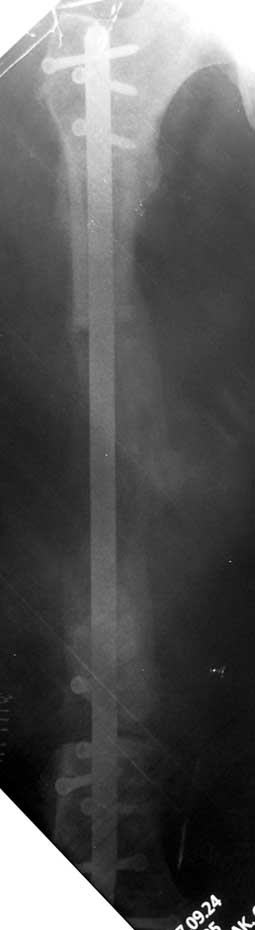

The duration of external fixation (external fixation index) depends on the amount of distraction required, and the extremity is prone to complications during this period. After the distraction phase is completed, the external fixator remains in place during the consolidation phase, which lasts twice as long as the distraction phase; but this period is hardly tolerated. If the external fixator is removed before sufficient consolidation is achieved, fractures, deformity and shortness will be the result. In our department, ‘lenghthening over nail’ method is used in order to decrease the external fixation index and increase patient comfort and activity level. In this method, the intramedullary nail is statically locked after the completion of the distraction phase, and external fixator is removed. The extremity is stabilized by the intramedullary nail during consolidation phase. In this way, complications due to long external fixation index or early removal of the external fixator are avoided.